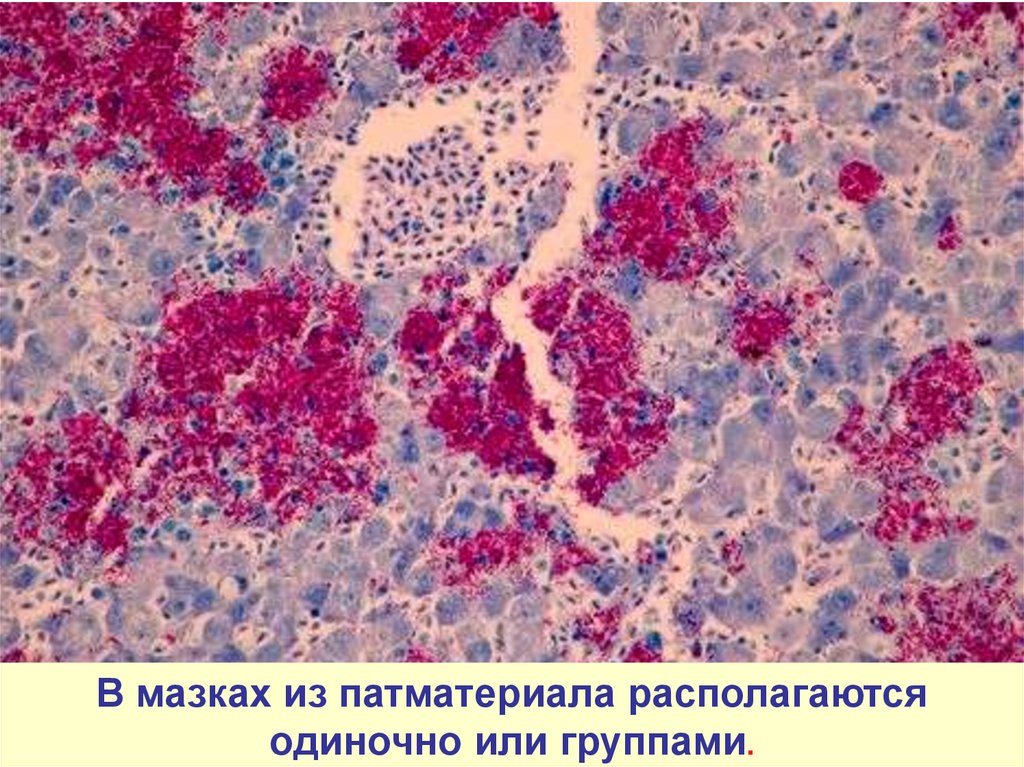

Микроскопический взгляд на мишитарный туберкулез легкого: фотодокументация

Раздел: Снимки-откровения